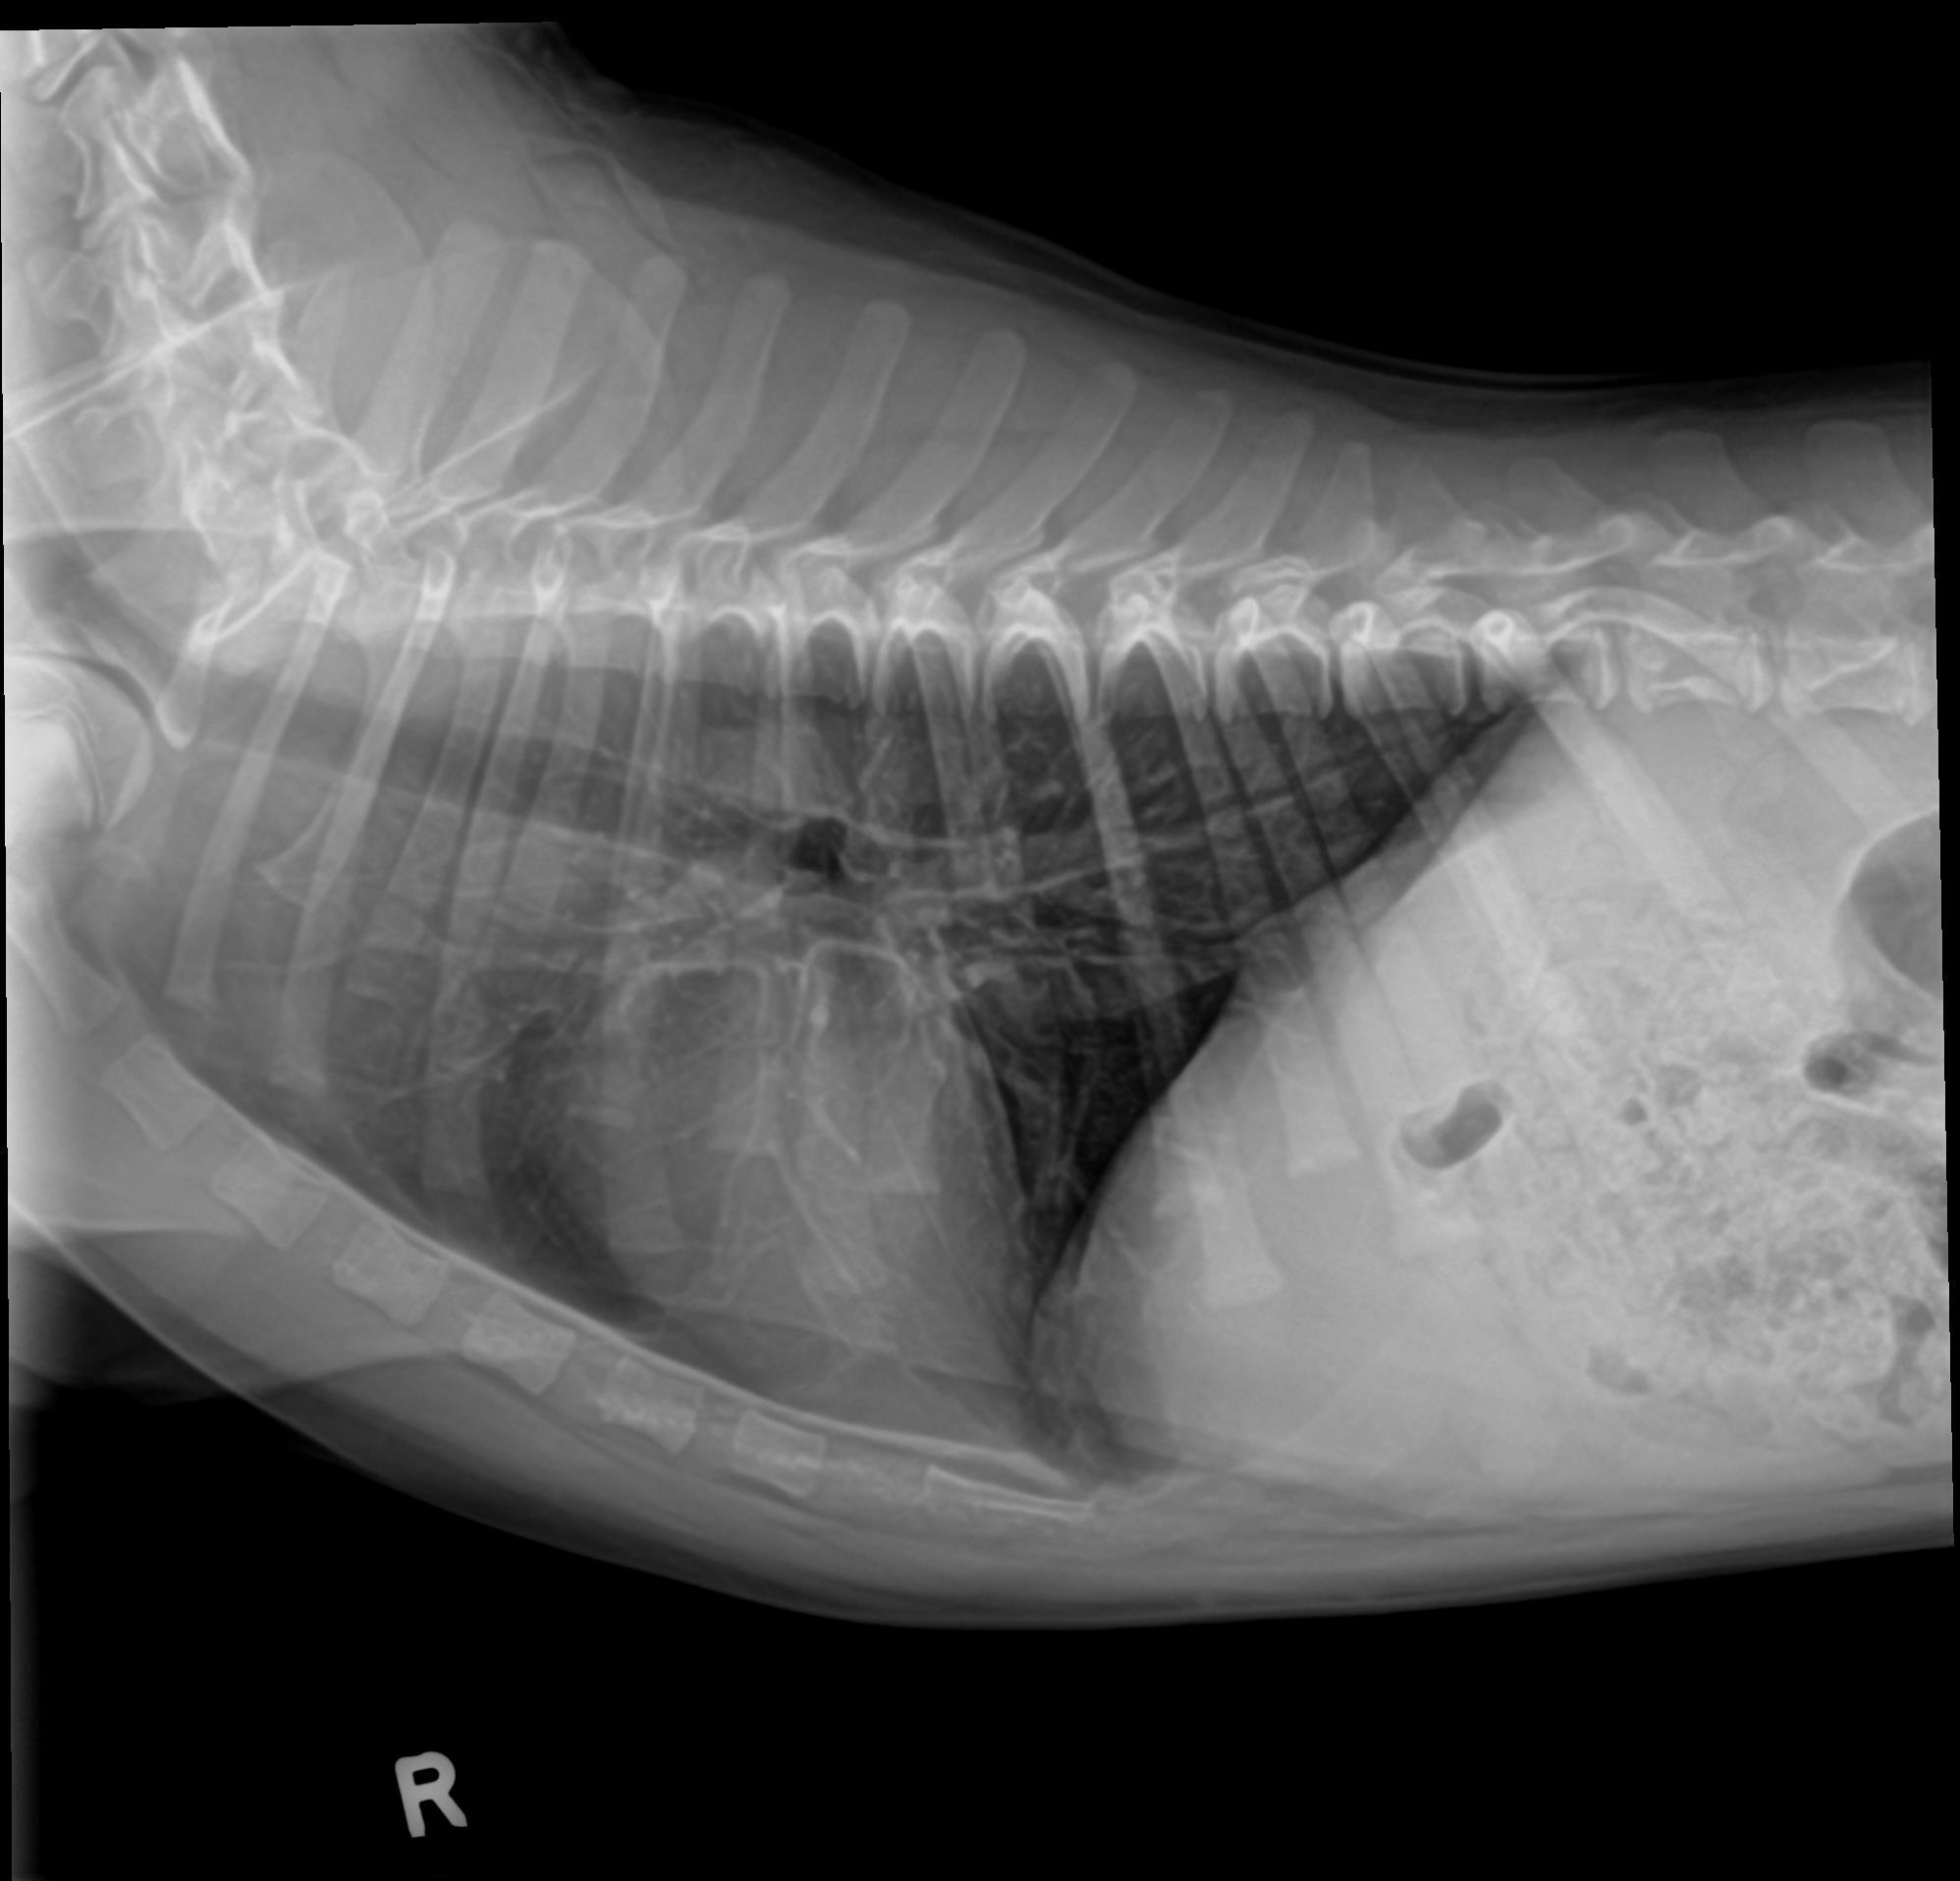

Physical exam findings and radiographs consistent with pneumonia.

Patient’s appetite and energy returned two days after starting additional therapy. Repeat radiographs at post-five days showed significant improvement as well.

Radiographs After Five Days of Treatment